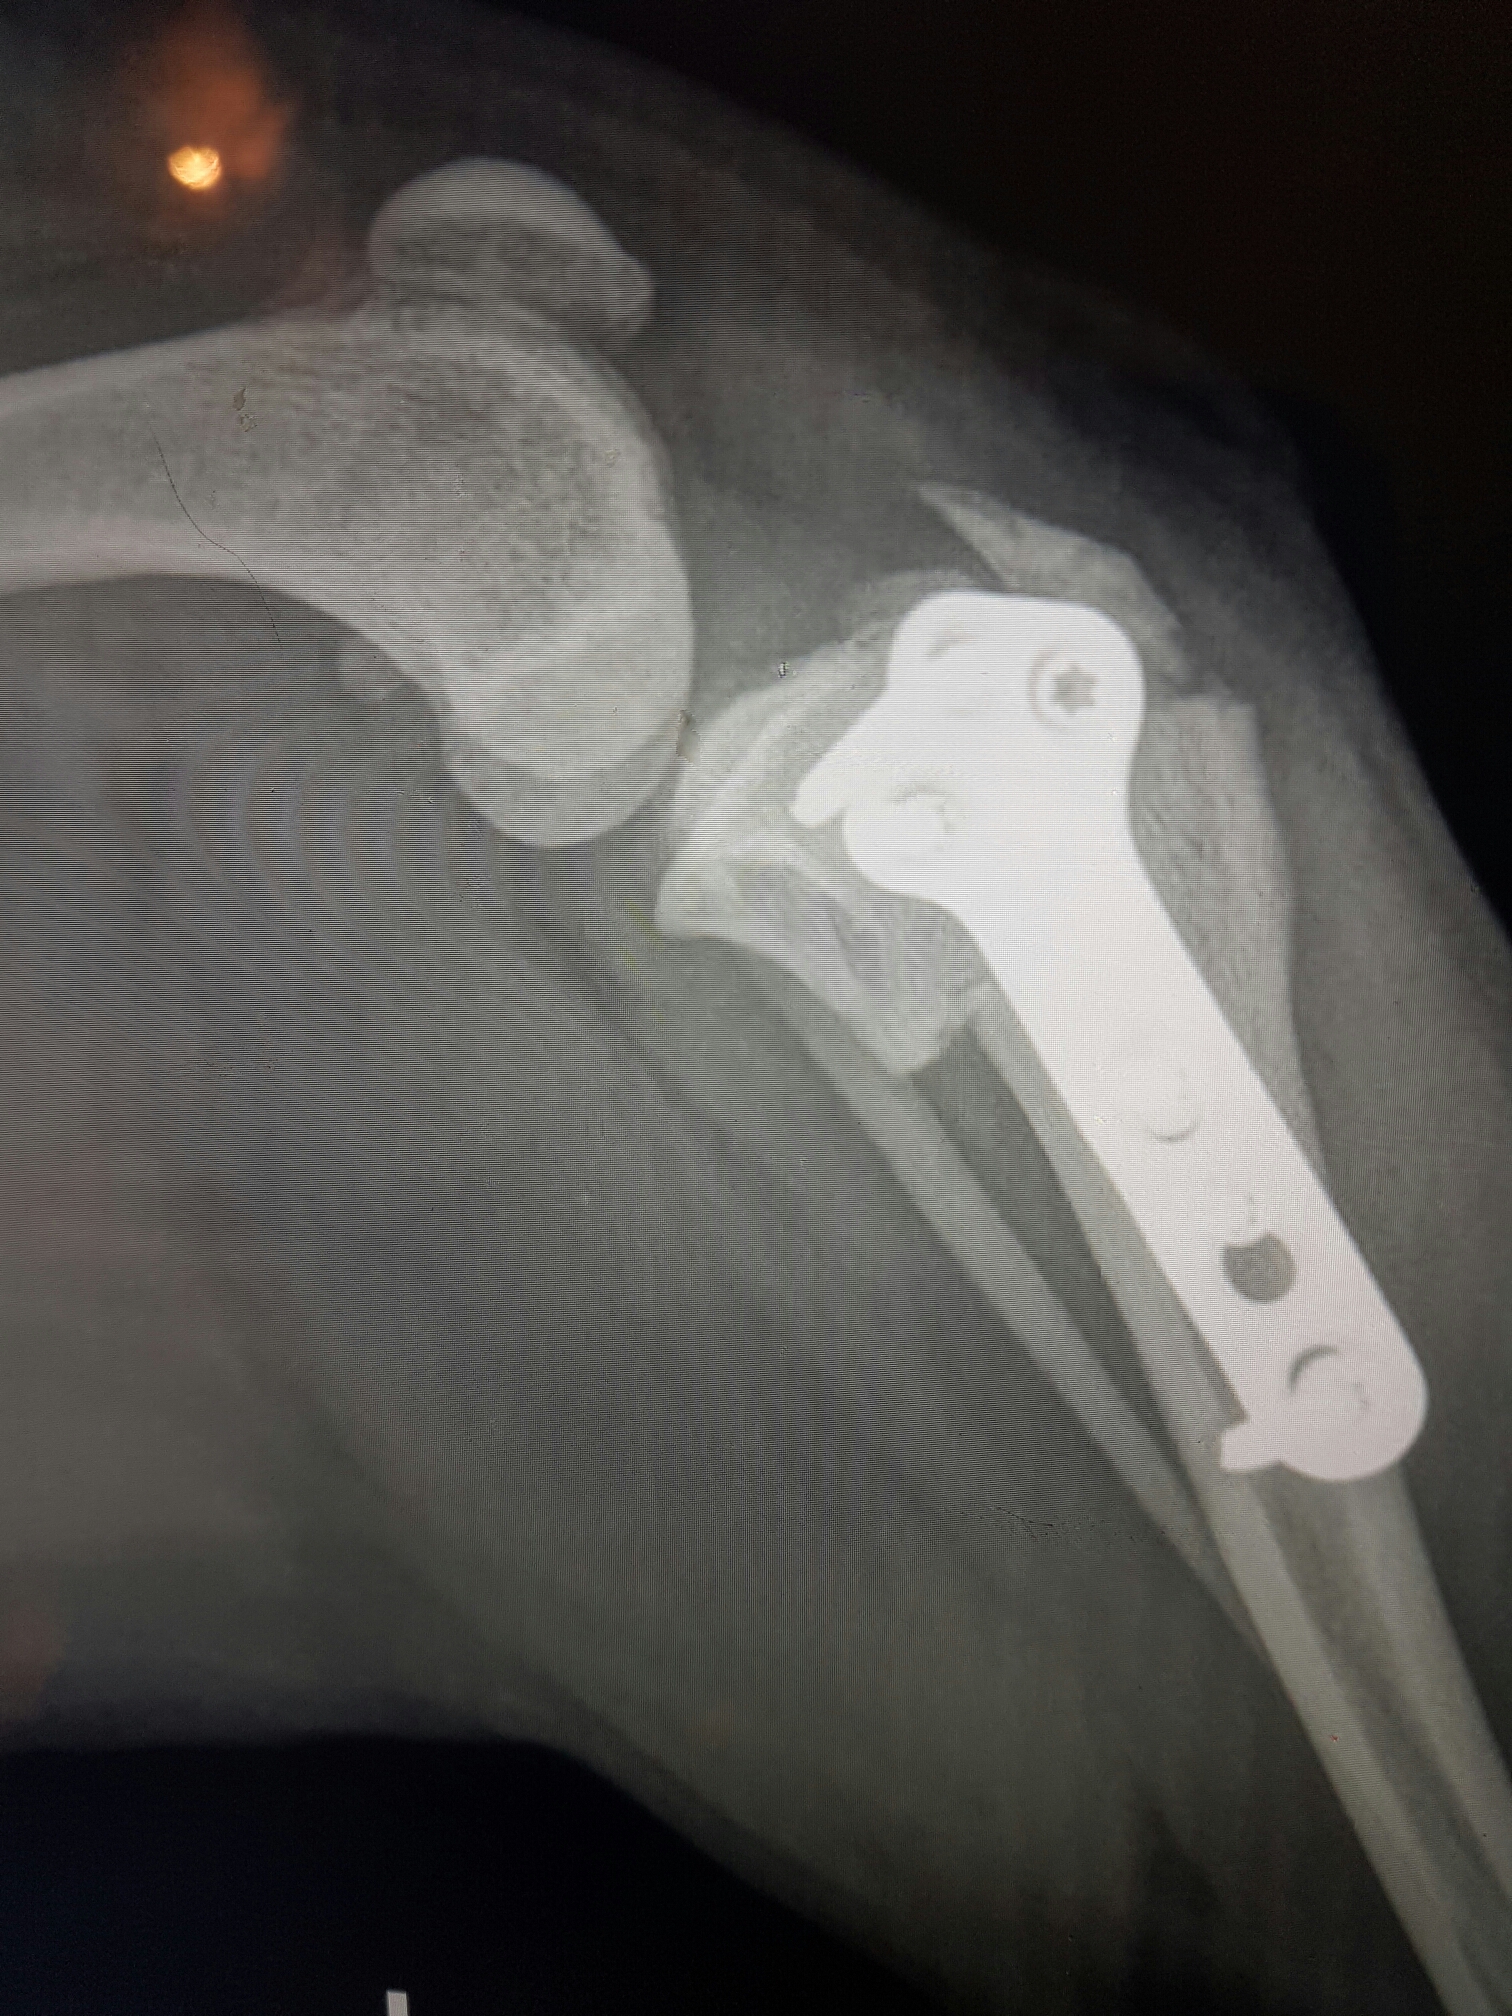

Han har fått gjort en TPLO – operasjon. Dvs at øverste del av leggbenet er saget over og satt på plass igjen i en litt annen vinkel slik at ikke korsbånd blir nødvendig. Herligheten blir så festet med en metallplate og seks skruer. Emil har gjort ettellerannet på den turen i hagen sånn at to skruer har løsnet og øverste del av leggbenet har fått seg en sprekk.. Det vil si at det hele er litt lealaust og at han i praksis går med et åpent brudd.